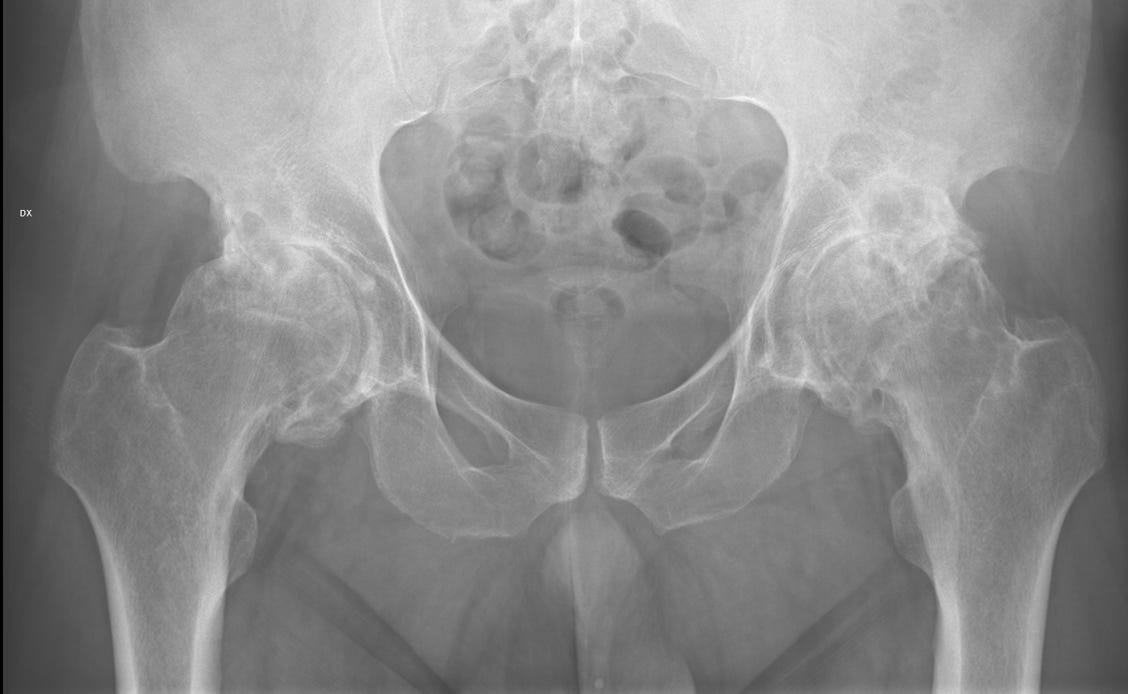

Artrosi anca, coxartrosi

Il conflitto femoroacetabolare (FAI) consiste in un insieme di alterazioni anatomiche dell’acetabolo e/o della testa del femore, che, soprattutto in pazienti che svolgono alcune attività sportive, determina una sindrome dolorosa associata a un aumentato rischio di artrosi precoce.

Artrosi dell’anca

Complicanze delle protesi di anca

Conflitto femoroacetabolare (FAI)